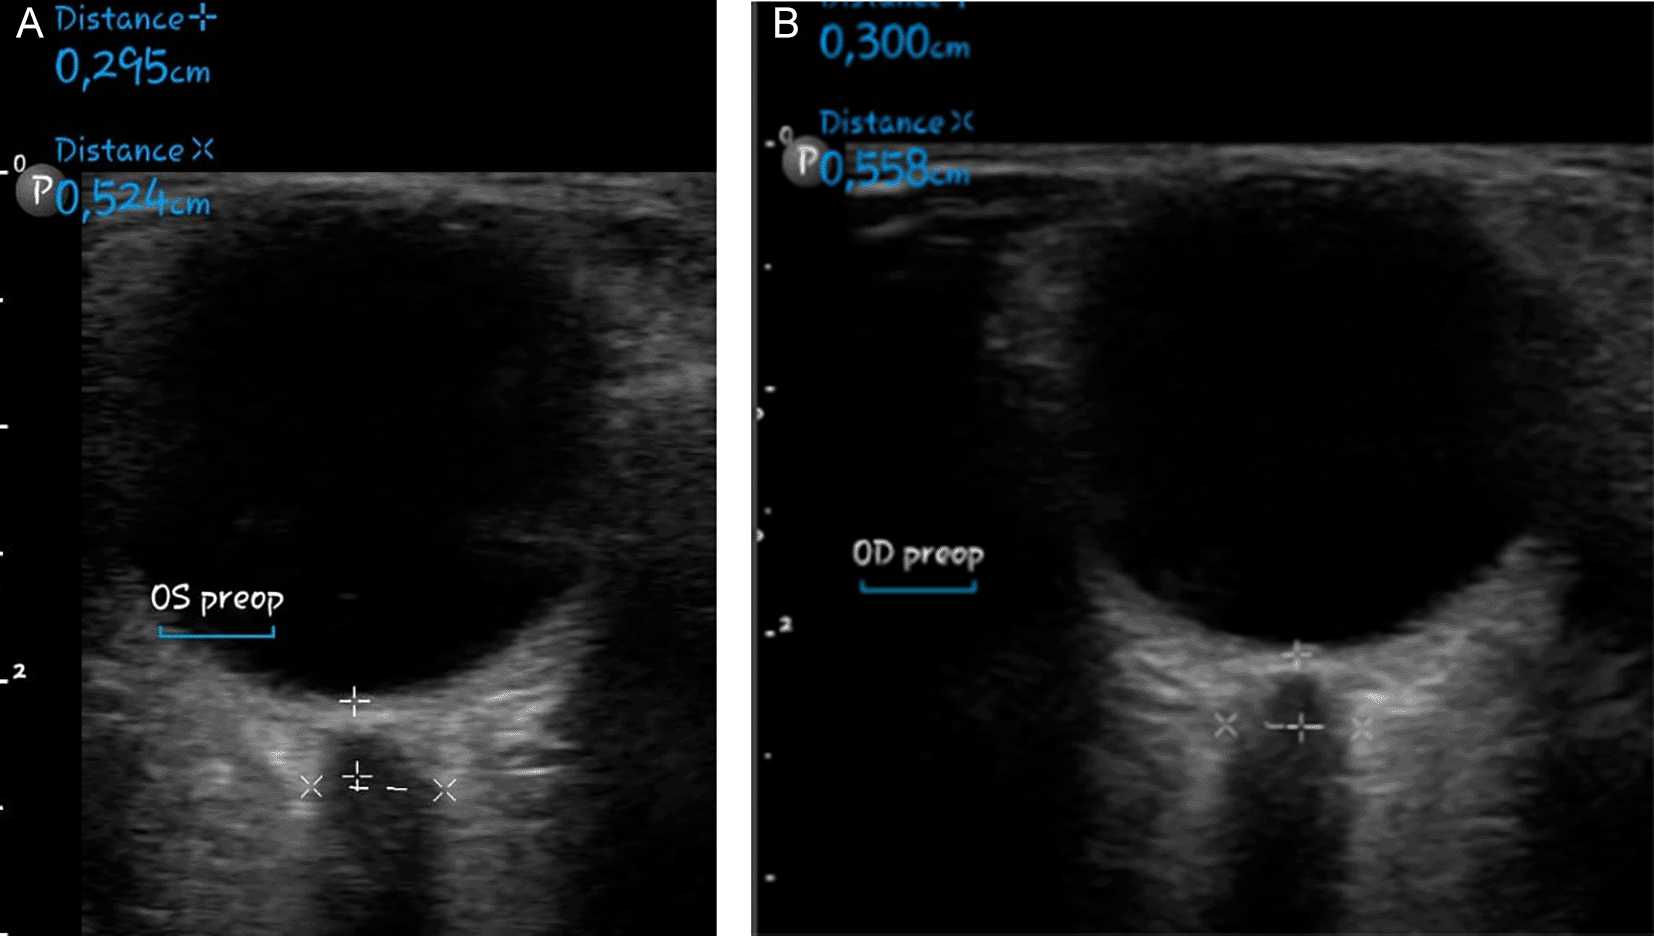

As a result of the tolerable GCS level of consciousness, the neurosurgery division postponed the surgery. Non-invasive hyperosmolar therapy was enhanced by administering mannitol every six hours, incorporating sedation with midazolam at a dosage of 0.1-0.5 mg/kg/hour, and providing Low Molecular Weight Heparin (LMWH) with an initial dose of 5000 IU, followed by 1 mg/kg every twelve hours, along with monitoring PT and APTT to achieve an INR target of 1.5 times the baseline APTT. Due to the absence of coagulability and the presence of persistent fever in the patient’s homeostatic function monitoring during anticoagulant medication, heparinization was terminated. We conducted sequential control CT scans and ultrasound assessments of the Optical Nerve Sheath Diameter (ONSD) to evaluate intracranial pressure (Figures 4-5). We administered third-tier therapy involving intubation, mechanical breathing, and barbiturate treatment, specifically continuous thiopental at a dosage of 1-5 mg/kg/hour ( Figure 6).

Our patient presented with diffuse acute headache, positional worsening, bilateral motor deficits, and thrombosis in the SSS with bifrontal hemorrhagic infarction, edema, and subcortical damage—confirmed via CT and MRI-MRV ( Figure 4). Her symptoms, lasting over one month, reflect rare prolonged ICP elevation and venous congestion.